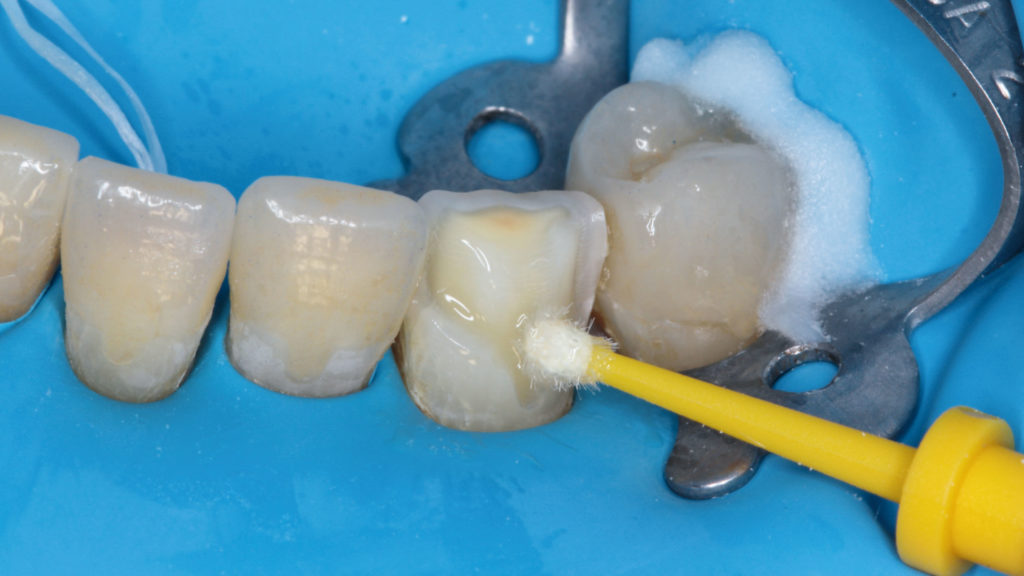

Im Labor konnten die vollkeramischen Restaurationen in der Presstechnik hergestellt werden (Abb. 8 bis 11). Die exakte Bisshöhe wurde zuvor im Mund evaluiert. Herstellung und Eingliederung der Veneers gestalteten sich dank des Wellenschliffs deutlich einfacher als mit anderen Veneer-Präparationsarten, da die Restaurationen am Zahn eine definierte Position hatten. Die adhäsive Eingliederung folgte den bekannten Abläufen. Die keramischen Restaurationen wurden geätzt beziehungsweise für das Verkleben konditioniert (Abb. 12). Nach dem Reinigen der Zähne wurden die Oberflächen mit Phosphorsäuregel vorbereitet, abgespült und getrocknet, mit Primer vorbehandelt, und es wurde Haftvermittler beziehungsweise Bonder aufgetragen (Abb. 13 bis 17). Nach dem Applizieren des Befestigungsmaterials konnten die Restaurationen eingegliedert und Materialüberschüsse entfernt werden (Abb. 18 und 19). Nach der Lichthärtung wurden die Ränder geglättet und die approximalen Kontakte angepasst sowie final poliert (Abb. 20 bis 24). Dabei zeigte sich ein weiterer Vorteil des Pfullinger Wellenschliffs. Der Übergang zwischen Zahn und Keramik ist dank des „diffusen“, bewusst unregelmäßig angelegten Präparationsdesigns optisch kaum wahrzunehmen. Eine Kontrolle der funktionellen Gegebenheiten bildete den Abschluss der prothetischen Therapie. Die in der Initialphase stabilisierte neue vertikale Bisshöhe konnte 1:1 mit den keramischen Restaurationen übernommen werden (Abb. 25).